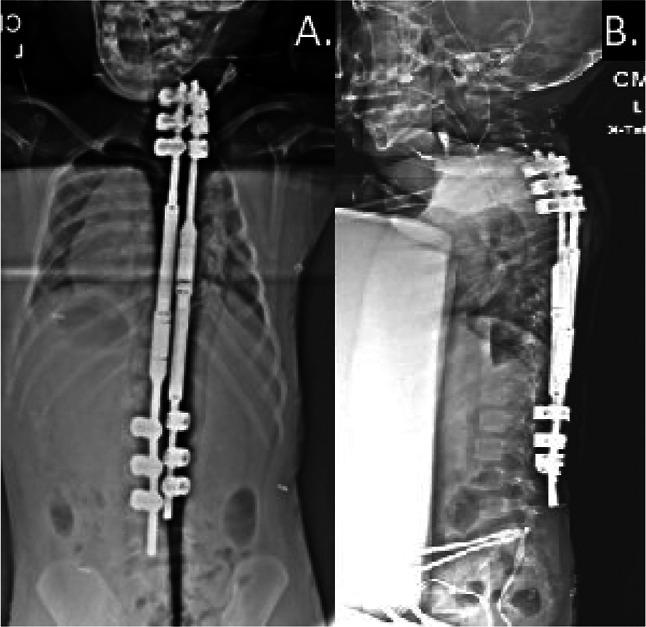

MAGEC rods (NuVasive) provide distraction growth in early-onset scoliosis. Pedicle screw use with MAGEC rods can lead to anchor failure. Sublaminar bands offer superior fixation points for the MAGEC system while preserving pedicles and facets, avoiding spinal cord injury, and eliminating the need for fluoroscopy. Sublaminar bands can be safely used up to cervical vertebra four (C4), substantially decreasing the risk of complications such as anchor pull-out, rod breakage, and proximal junctional kyphosis that typically occurs with pedicle screws and hooks. This case demonstrates the viable option of sublaminar band fixation as an anchor system for MAGEC rods. This is a retrospective case review of one patient with early-onset scoliosis who underwent multiple osteotomies, spinal cord decompression, and placement of MAGEC rods with sublaminar bands. The patient had successful distraction procedures conducted routinely throughout a 44-month period with no associated implant complications or neurologic sequelae during that period. The patient had achieved maximal distraction with the implanted rods and thereafter underwent removal of the MAGEC rods and replacement implantation with longer MAGEC rods. The purpose of this case review was to demonstrate the superior fixation results provided with sublaminar band fixation for MAGEC rod distraction systems.

MAGEC 棒(NuVasive)可提供早期脊柱侧凸的生长分离。MAGEC 棒与椎弓根螺钉的使用可能导致锚定失败。 皮下带为 MAGEC 系统提供了更优越的固定点,同时保留了椎弓根和关节突,避免了脊髓损伤,并消除了透视的需要。皮下带可以安全地用于 C4 颈椎,大大降低了通常与椎弓根螺钉和钩子相关的并发症风险,如锚钉拔出、棒断裂和近端交界性后凸。 该病例展示了皮下带固定作为 MAGEC 棒锚定系统的可行选择。这是一名患有早期脊柱侧凸的患者的回顾性病例报告,该患者接受了多次截骨术、脊髓减压和 MAGEC 棒皮下带固定。在 44 个月的时间内,患者成功地进行了常规的分离手术,在此期间没有出现与植入物相关的并发症或神经后遗症。患者通过植入的棒获得了最大的分离,此后进行了 MAGEC 棒的移除,并更换为更长的 MAGEC 棒。本病例回顾的目的是展示皮下带固定在 MAGEC 棒分离系统中的固定效果。